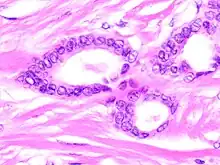

Tubular carcinoma is a subtype of invasive ductal carcinoma of the breast.[2][3] More rarely, tubular carcinomas may arise in the pancreas[4] or kidney.[5] Most tubular carcinomas begin in the milk duct of the breast and spread to healthy tissue around it.[6][7]

Tubular carcinomas are generally around 1 cm. or smaller, and are made up of tubules. They are usually low-grade.[2] Elastosis has been noted as common but is not present in all cases.[11]

A highly differentiated invasive carcinoma that forms well-defined tubules (containing epithelium, but no myoepithelium) and that have abundant desmoplastic fibrous stromal reaction between the tubules.